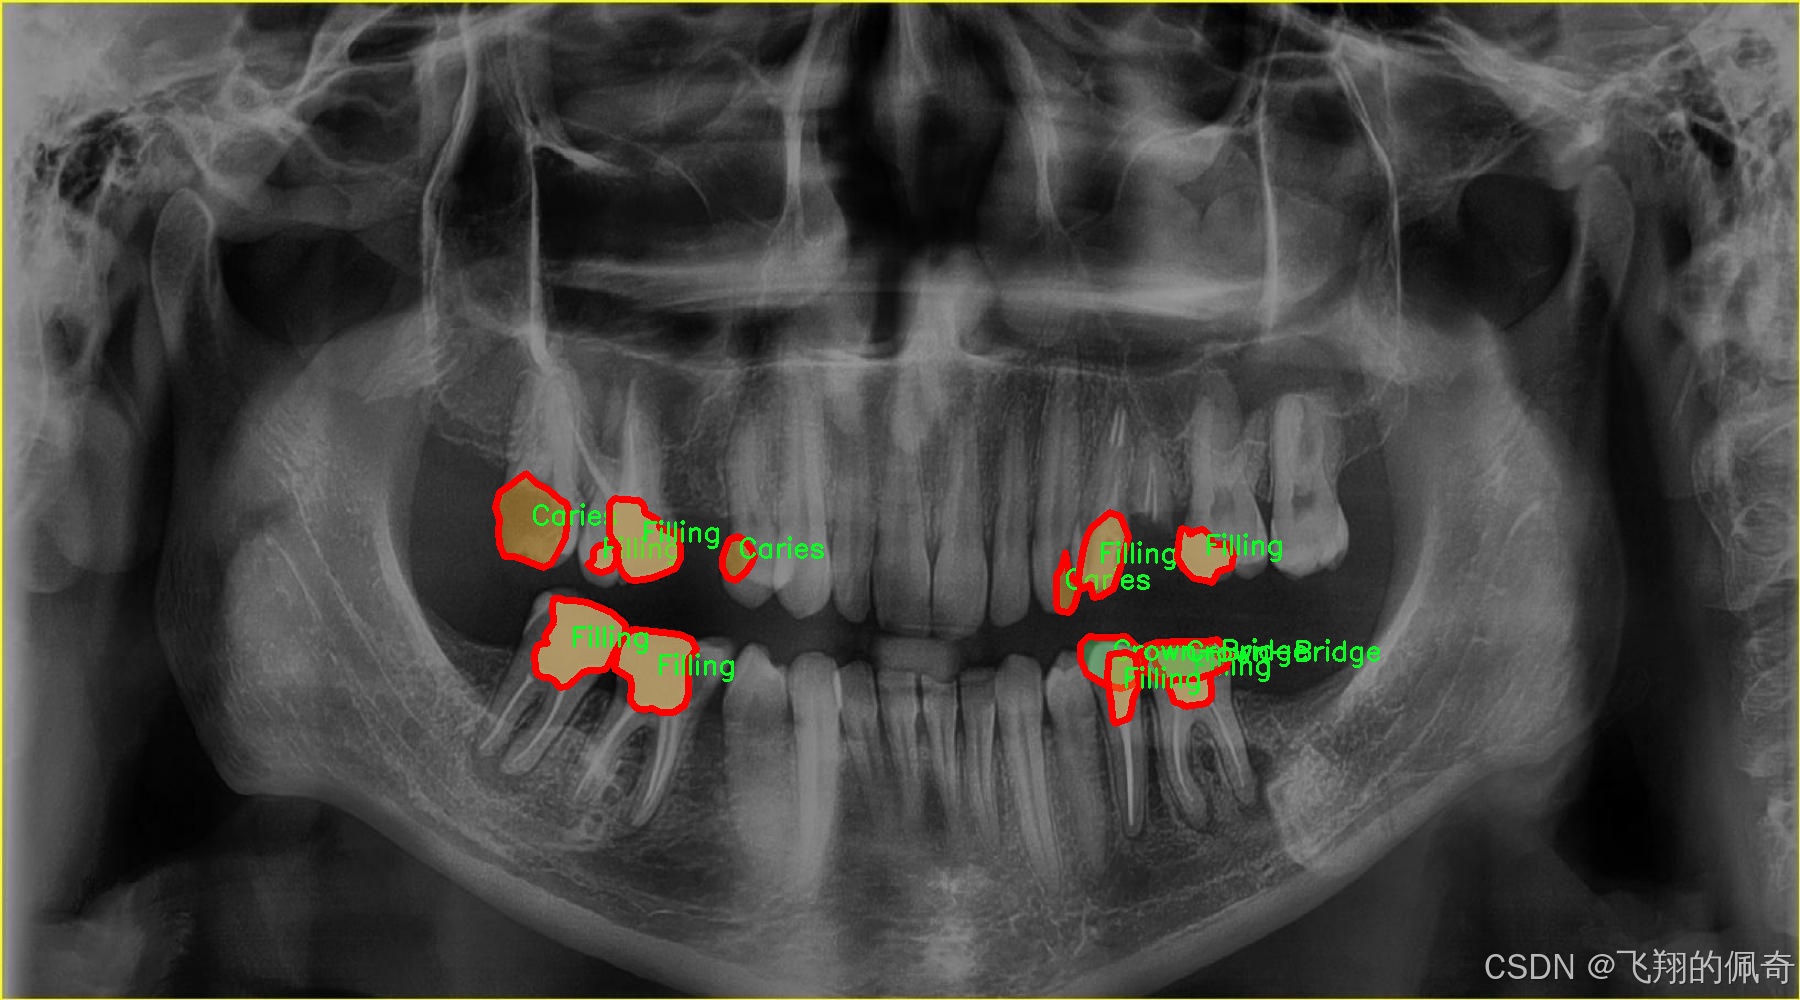

图片效果

在现代牙科医学中,龋齿的早期诊断与治疗至关重要,而图像分割技术在这一领域的应用为牙科医生提供了更为精确的工具。为此,我们构建了一个名为“tooth segmentation”的数据集,旨在训练改进版的YOLOv8-seg模型,以实现对牙齿病变图像的高效分割。该数据集专注于八种不同的牙齿病变类型,涵盖了从龋齿到各种修复体的多样性,确保模型能够识别和分割这些关键特征。

“tooth segmentation”数据集包含八个类别,分别为:龋齿(Caries)、牙冠与桥(Crown-Bridge)、填充物(Filling)、植牙(Implant)、后螺钉(Post-screw)、根管填充(Root canal Obturation)、牙冠(crown)以及再植体(implant)。这些类别不仅代表了牙齿的不同病变状态,还涵盖了牙科治疗中常见的修复和重建过程。这种多样性使得数据集在训练过程中能够有效地提高模型的泛化能力,帮助其在实际应用中更好地适应不同的病例。